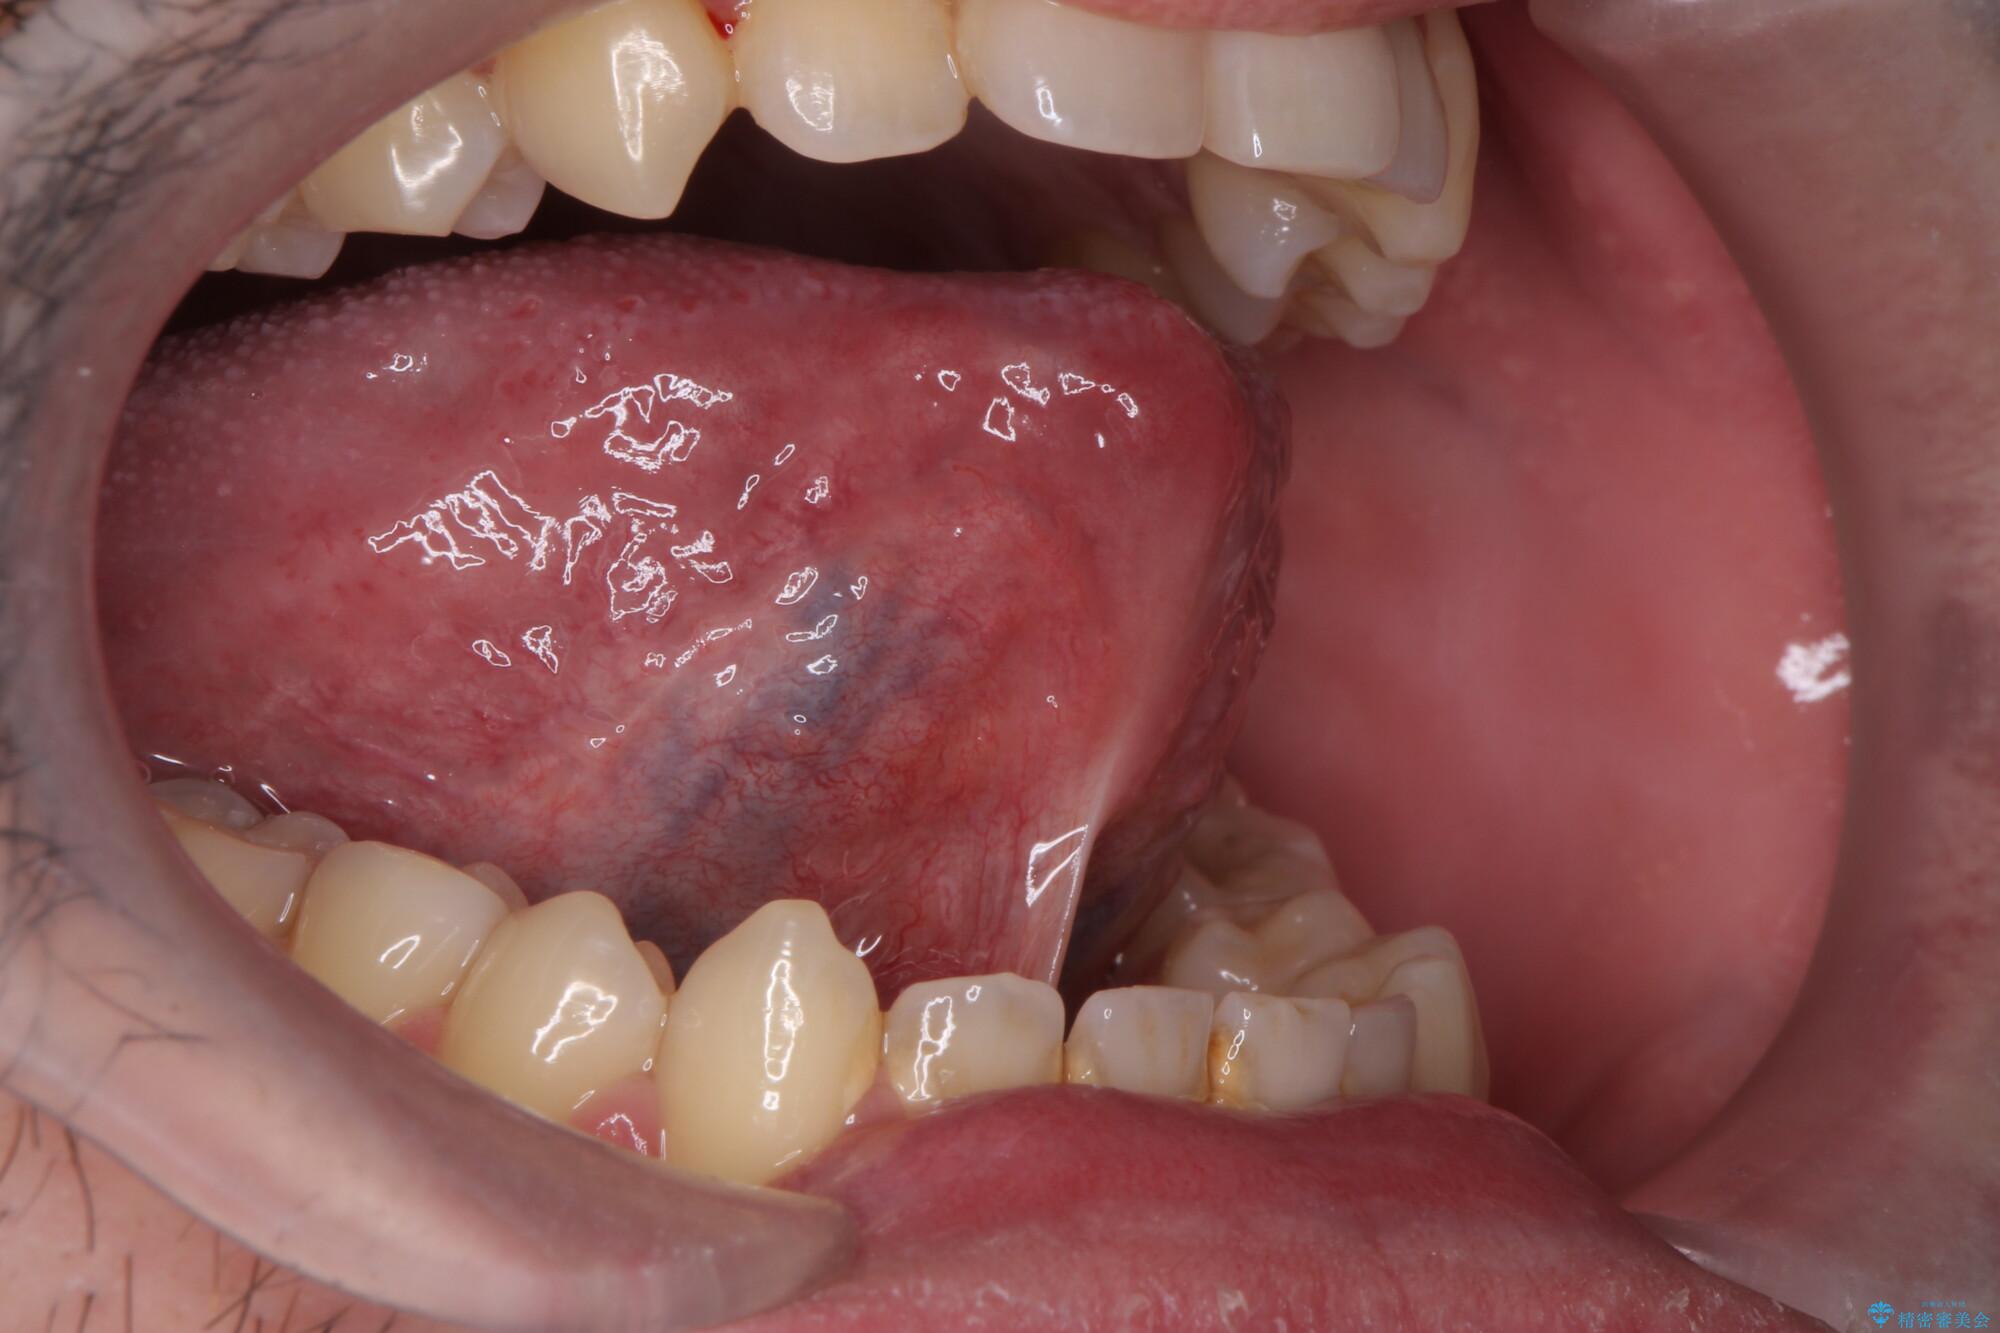

治療後

舌小帯を切除し滑舌を治したい 治療後画像 舌小帯を切除し滑舌を治したい 治療後画像